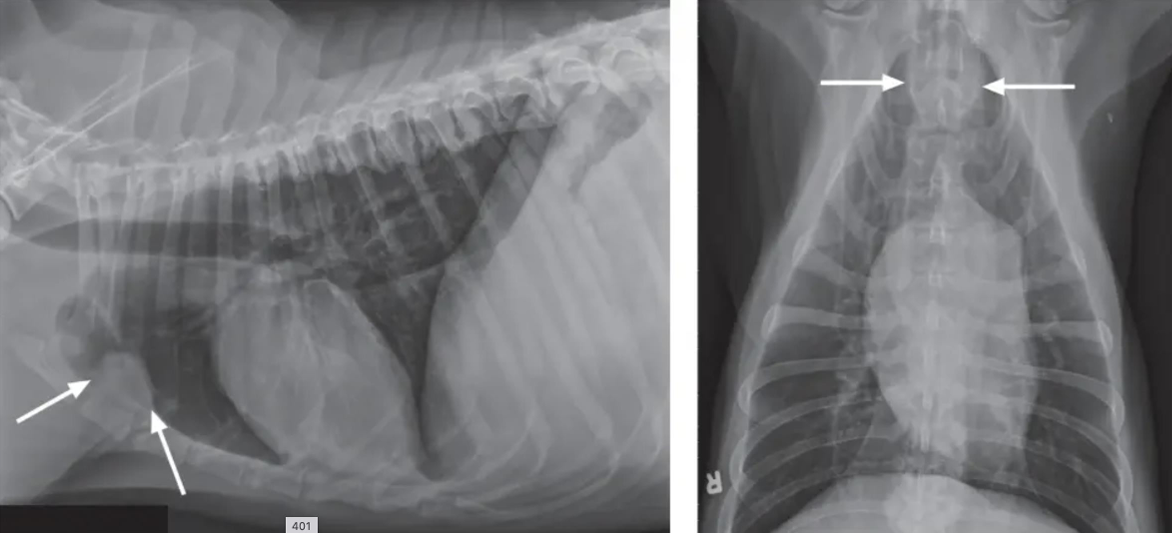

![]() | Pneumothorax - 폐가 쪼그라들면서 하얗게 보임 - 심장이 떠 있음 |

![]() | Pneumomediastium - 종격동에도 공기가 참 - 평소 안 보이던 식도, 대동맥 가지, 전대정맥 등도 보임 - 하얀 화살표는 흉관 tube를 장착해 놓은 것 - 임상적으로 큰 의의는 없음 - 종양 때문에 넓어질 때가 가장 많음. 비만일 수도 있음. |